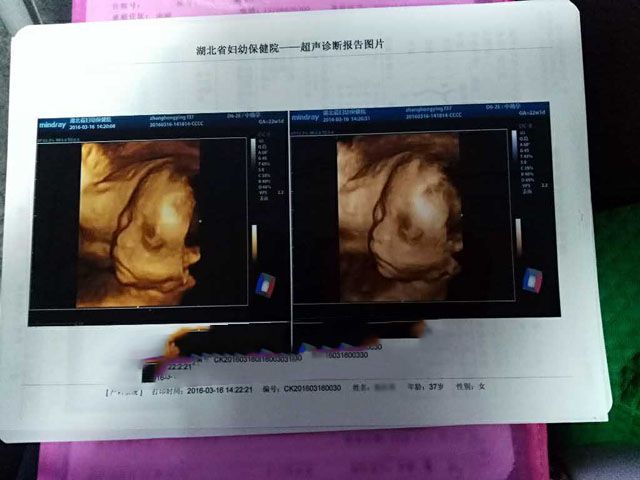

要不要看看产检记录!

2016年7月4日,孕37周,男宝宝顺利降临。